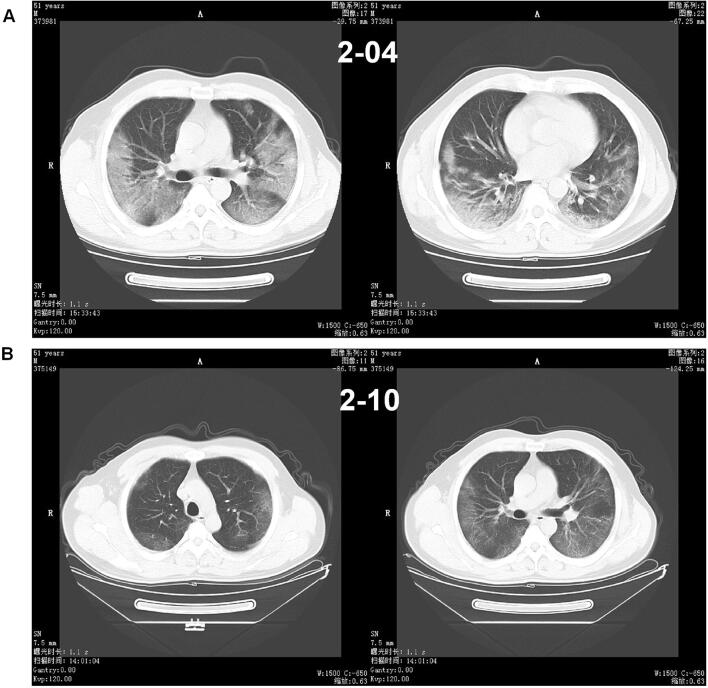

Among the 194 patients, 141 (72.68%) showed abnormal chest CT images, consisting of 101 cases (52.06%) of bilateral pneumonia and 40 cases (20.62%) of unilateral pneumonia (Table 1). Some lesions might have a mixed pattern of consolidation in the center and ground glass opacity in the periphery (Fig. 1). In severe or critically severe patients, multiple patches or an integrated larger patch of ground glass opacity, consolidation or mixed consolidation and ground glass opacity might present in bilateral lungs (Fig. 2).

Fig. 1.

Chest CT of a male patient, 51 years old. a He underwent a chest CT examination on February 4, which showed a piece of peripheral ground glass opacity with consolidation in the lower lobes of the two lungs. b 6 days after treatment, the CT images of February 10 showed a decrease in density of the pulmonary lesions with fibrosis formation